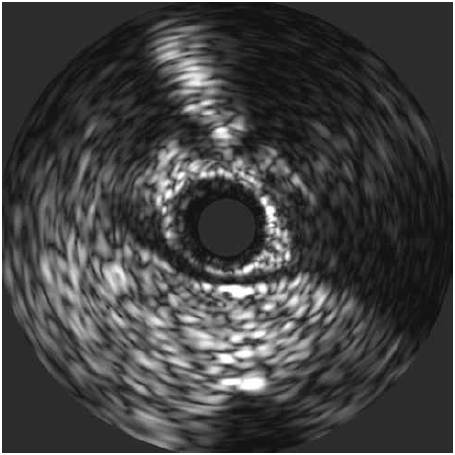

- Ecografía intracoronaria

Una técnica diagnóstica novedosa, poco disponible en nuestro medio; pero con ventajas diagnósticas sobre otros métodos.

El hallazgo característico es el signo de “media luna”, un área ecolúcido presente sólo entre el segmento coronario puenteado y el tejido epicárdico que persiste durante todo el ciclo cardíaco. Además, la ecografía intravascular puede caracterizar la aterosclerosis subangiográfica proximal (Figura 1).